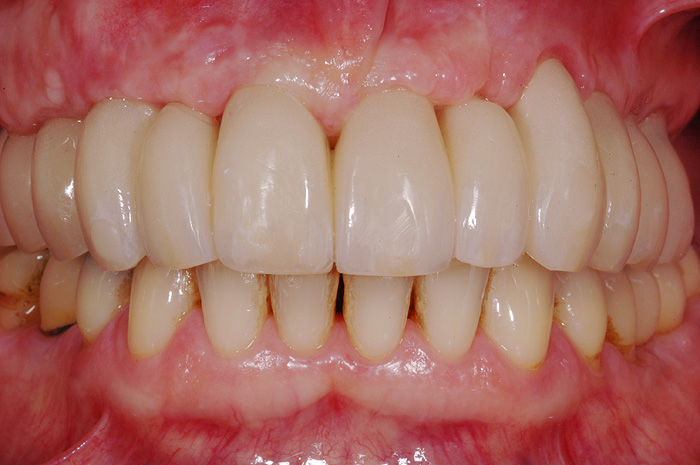

Gesamtrekonstruktionen

Fehlen in einem Kiefer alle Zähne oder sind die meisten Zähne in einem schlechten, nicht erhaltungswürdigen Zustand, ist es sinnvoll eine Gesamtrekonstruktion anzufertigen. Diese kann sowohl dental als auch implantat-getragen sein. Die Gesamtrekonstruktionen sind zeitlich wie finanziell aufwendig, bestechen aber durch ihre Ästhetik und die Langlebigkeit. Der Vorteil ist, dass viele kleine Arbeiten und Reparaturen in den nächsten Jahren wegfallen werden.

Fallbeispiel

Zum Vergrössern klicken